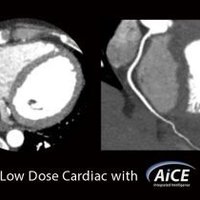

Mit AiCE, kurz für Advanced intelligent Clear-IQ Engine, kann der Aquilion One PRISM Edition besonders scharfe, klare und präzise Bilder in kürzester Zeit gewinnen. Die KI unterstützt die Reduktion von Bildrauschen auf ein Minimum und ermöglicht klare Aufnahmen mit sehr gut erkennbaren Strukturen auch bei niedrigem Kontrast. Gleichzeitig bringt sie eine automatische Anpassung des Kontrasts mit sich. Weiterhin ermöglicht sie eine schnelle kV-Umschaltung und eine patientenspezifische mA-Modulation, die wiederum mit einer Deep Learning-Rekonstruktion kombiniert wird, um eine hervorragende Energietrennung zu erzielen und Bildrauschen weiter zu reduzieren.

Neben der Qualität der Aufnahmen steht beim Aquilion One PRISM Edition auch die Effizienz im Fokus. So reicht eine einzige Rotation aus, um ein komplettes Herz darzustellen. Dabei wird sowohl die Dosisbelastung reduziert, als auch eine außerordentliche Gleichmäßigkeit der z-Achse garantiert. Die schnelle Bildgebung kommt besonders in der Behandlung von Schlaganfallpatienten zum Tragen, wo jede Sekunde zählt, um Hirngewebe zu retten.